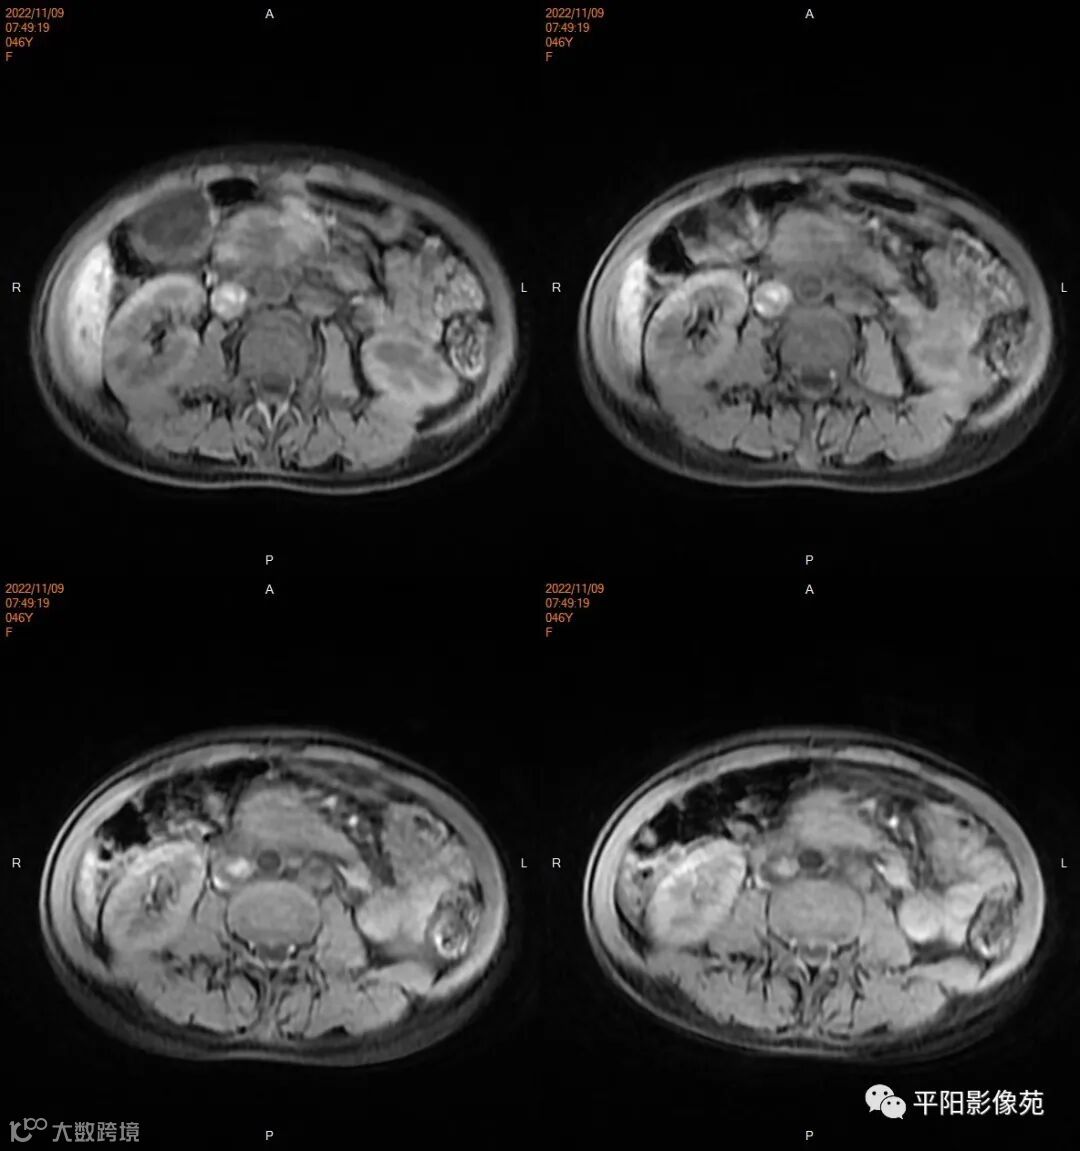

影像学检查

MR

影像表现: